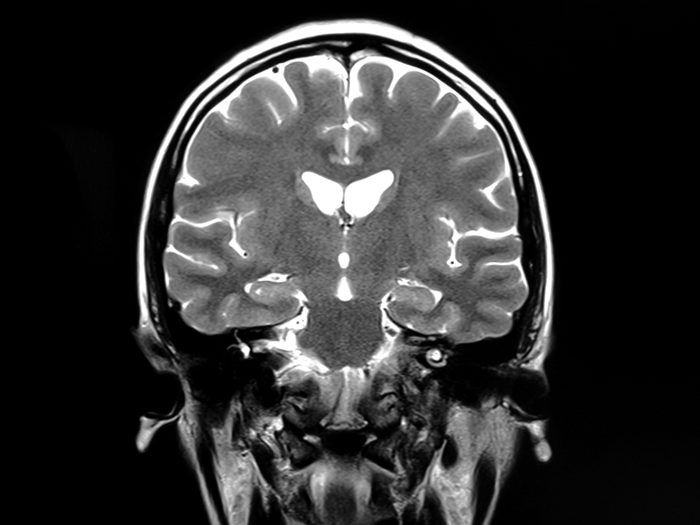

Subarachnoid hemorrhage

Hemorrhaging is terrible wherever it may occur, but it’s particularly bad when it happens in the space between the brain and its protective tissues. Shoulder pain is one possible symptom, but it’s not the most common. The same goes for neck pain, vision problems, numbness, confusion, sensitivity to light, nausea, and seizures (among others), according to Harvard Medical School. But the telltale sign of a subarachnoid hemorrhage (SAH) is a sudden and debilitating headache. This condition can be caused by a brain aneurysm, trauma, or blood thinners, and you’ll need immediate medical intervention to prevent brain damage and save your life.